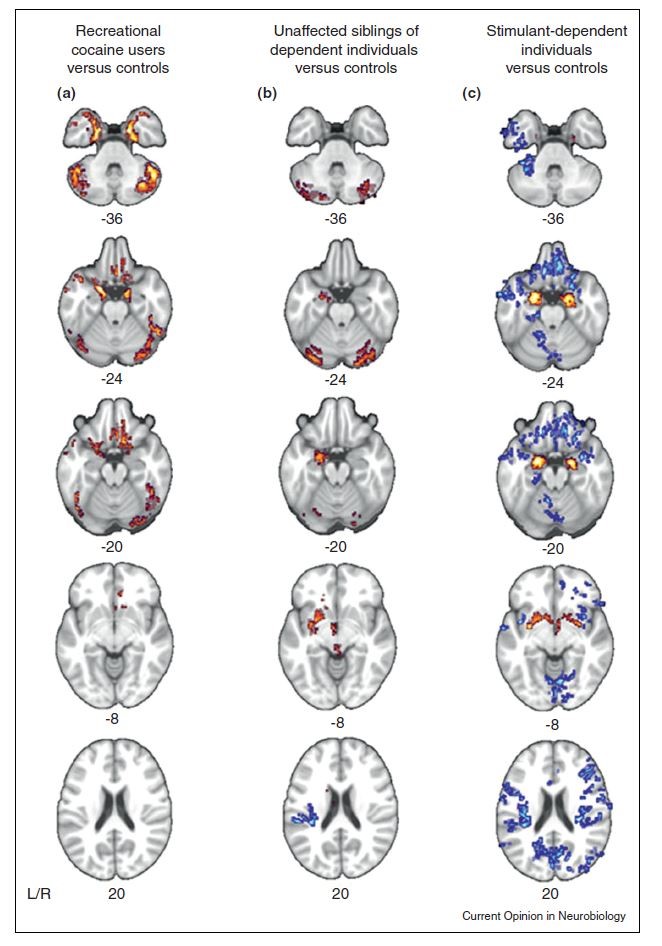

자극제 의존과 관련된 연구 결과에서는 자기 조절과 관련된 전두엽의 부피감소가 관찰되고 있습니다. 약을 사용해서 의존이나 남용이 생겼느냐, 아니면 약물관련 문제에 선행해서 이러한 구조적 문제가 있느냐는 논란거리이지만, 최근까지의 연구에서는 대개 충동조절의 어려움을 가지고 있는 사람이 이러한 것에 노출되었을 때 의존과 남용 등이 발생한다는 것으로 보고 있습니다. 따라서 성인ADHD로 진단을 받은 경우, 기존에 물질(술 포함) 관련 문제가 심각하지 않았다면 자극제 사용으로 인한 오남용, 의존 가능성은 크게 걱정하지 않아도 되겠습니다.